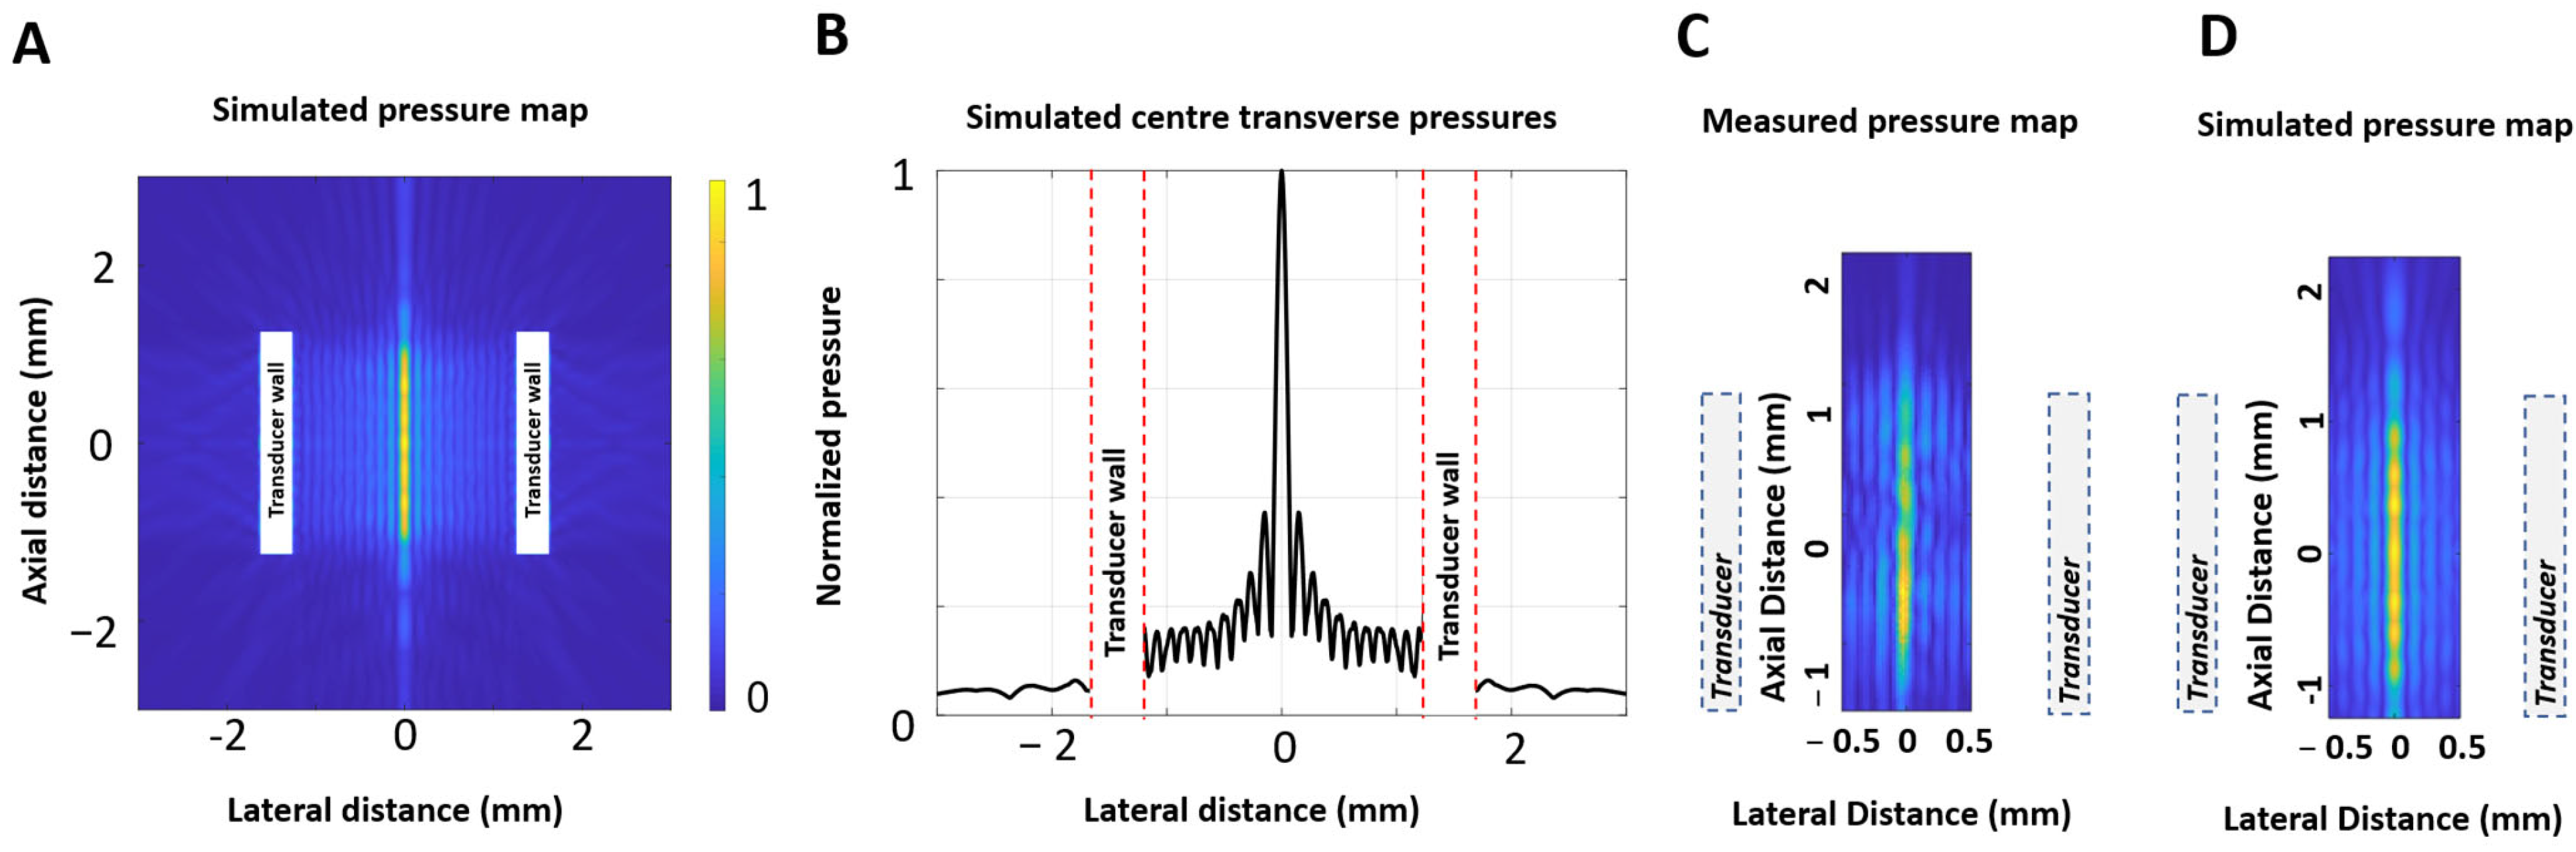

2.1. Transducer Configuration

2.2. Cavitation Observation with High-Speed Ultrasound Imaging

2.2.1. Experimental Configuration

2.2.2. Transmit Frequency Selections